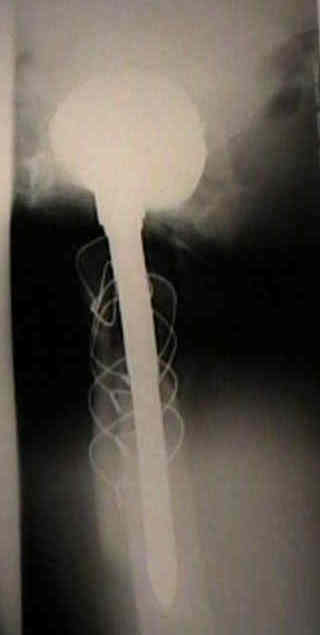

Loosening of Press Fit Acetabular Components

(press fit acetabular components)

radiographic signs of loosening

(see also: radiographic techniques for eval of acetabulum)

- radiolucent lines that initially appeared after two years

- progression of radiolucent lines after two years

- radiolucent lines in all three zones

- radiolucent lines 2 mm or wider in any zone

- migration

- loosening is present w/ more than 2 mm of migration (either horizontal or vertical);

- continuous radiolucent line;

- note that peripheral radiolucent lines which are non-continuous are commonly found in press fit acetabular components and are often not progressive;